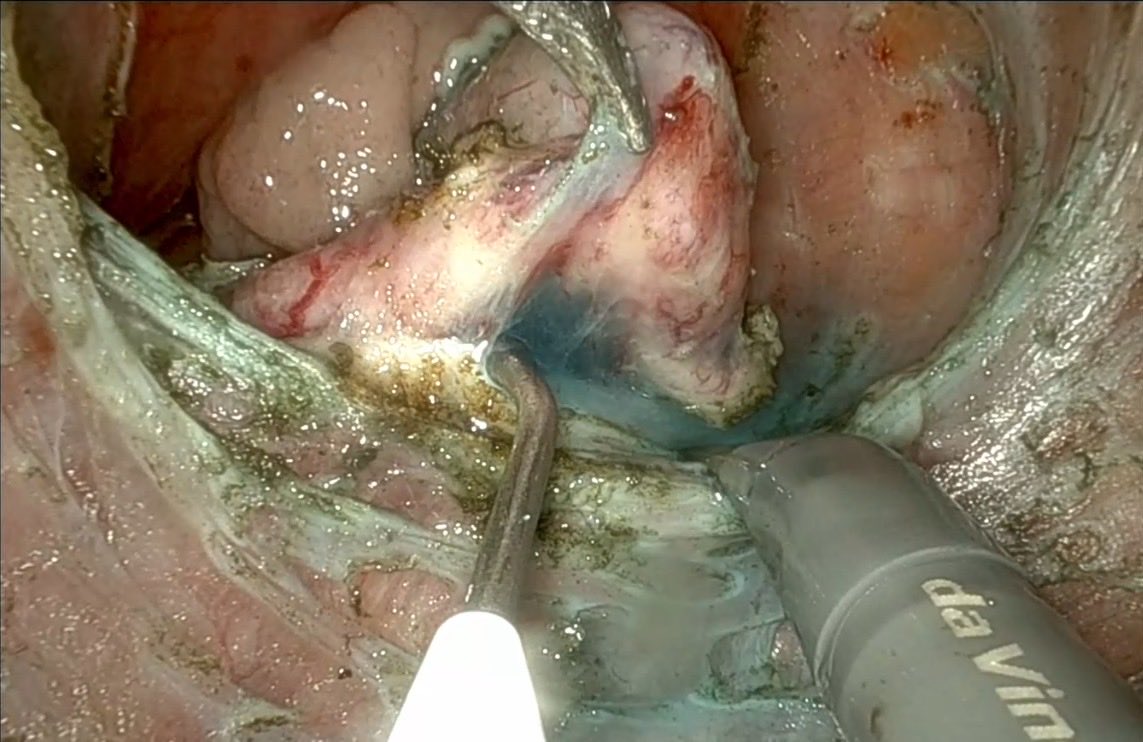

R-TAMIS para excisión de pólipos rectales. Publicado en @ColorectalDis 📍 https://t.co/2QdaB86elK

Nueva publicación en @ColorectalDis En esta ocasión TAMIS robótico con hidrodisección 📍 https://t.co/CKwK7p8ABX